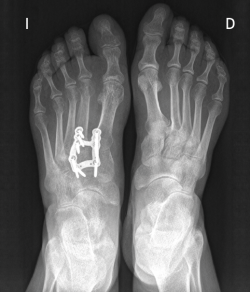

rpt.3502.fs2104013-figura1.png

Figura 1. Artrosis primaria de la primera articulación cuneometatarsiana.

rpt.3502.fs2104013-figura2.png

Figura 2. Tratamiento quirúrgico mediante artrodesis con placa en proyección dorsoplantar.

Existen distintas opciones de osteosíntesis con tornillos y/o placas. Actualmente, disponemos de diferentes diseños de placas: placas de tipo “Pi” que fijan CMM1-CMM2, placas plantares, mediales, medioplantares o dorsales. Recomendamos el empleo de placas “Pi” si es preciso artrodesar CM-M2 y el uso de placas medioplantares o plantares para la artrodesis aislada de CM-M1, que desde el punto de vista biomecánico son más apropiadas (Figuras 1 a 3). Otro tema de debate es el empleo de injerto óseo esponjoso autólogo o de sustitutivos óseos como la matriz ósea desmineralizada o trifosfatos cálcicos. Recomendamos, especialmente en pacientes menores de 50 años, el empleo de injerto autólogo de cresta ilíaca.